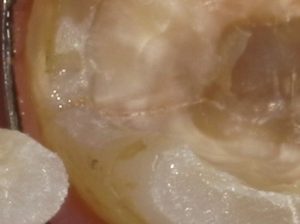

この状態ではよくわからないが拡大してみると

遠心にクラックがあるのが認められる。メチレンブルーにて染色を行った。

染色した遠心部を拡大してみると明らかにクラックがはいっているのが分かる。